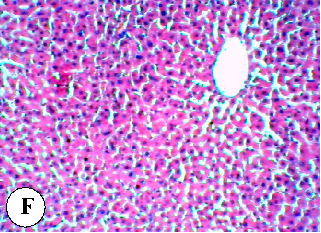

Figure 6

Figure 6 Micrograph

Liver tissue sections from rats co-treated with diazinon and a plant oil, showing varying degrees of protection against pesticide-induced hepatic damage.

Protective effect of some plant oils on diazinon induced hepatorenal toxicity in …